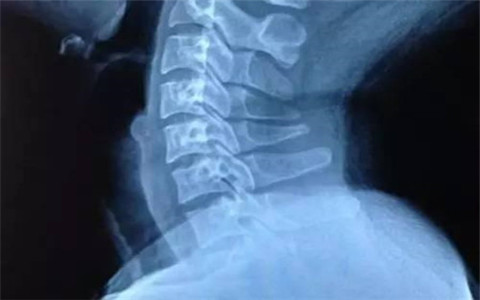

頸部是人們身體非常重要的部位,它是連接頭部與身體的交點,頸部一旦受到傷害可能會影響到整個身體。頸部是十分脆弱的,如今越來越多的人患上了頸椎病,對我們的工作和生活造成嚴重的影響。頸椎病的種類有很多種,今天我和大家說的是頸椎生理曲度變直。

我們?nèi)绾稳ダ斫膺@一概念呢?從表面看一個人在端坐或者站立時頸部似乎都是直的,但是包繞于內(nèi)部的頸椎并不是直的,其中中斷有一向前突出的弧度。在醫(yī)學上這一弧度就被稱為頸椎的生理曲度。所以正常的頸椎是一個向前凸起的C字型結(jié)構(gòu),為什么會是這樣也是在人類的進化過程中逐漸形成有利于我們的特征,這種形狀可以增加頸椎的彈性,減輕和緩沖重力的作用,從而防止對脊髓和大腦的損傷。但是現(xiàn)在人們不合理的使用頸椎,如長期低頭,不當?shù)乃咦藙莼蛘呔米榷紩诡i椎的生理曲度發(fā)生改變,致使頸椎的前凸消失,進而形成頸椎的生理曲度變直的情況。